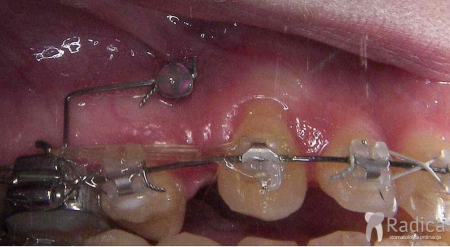

Uspravljanje nagnutog umnjaka pomoću mikroimplantata da zauzme mjesto prethodno izvađenog drugog molara: